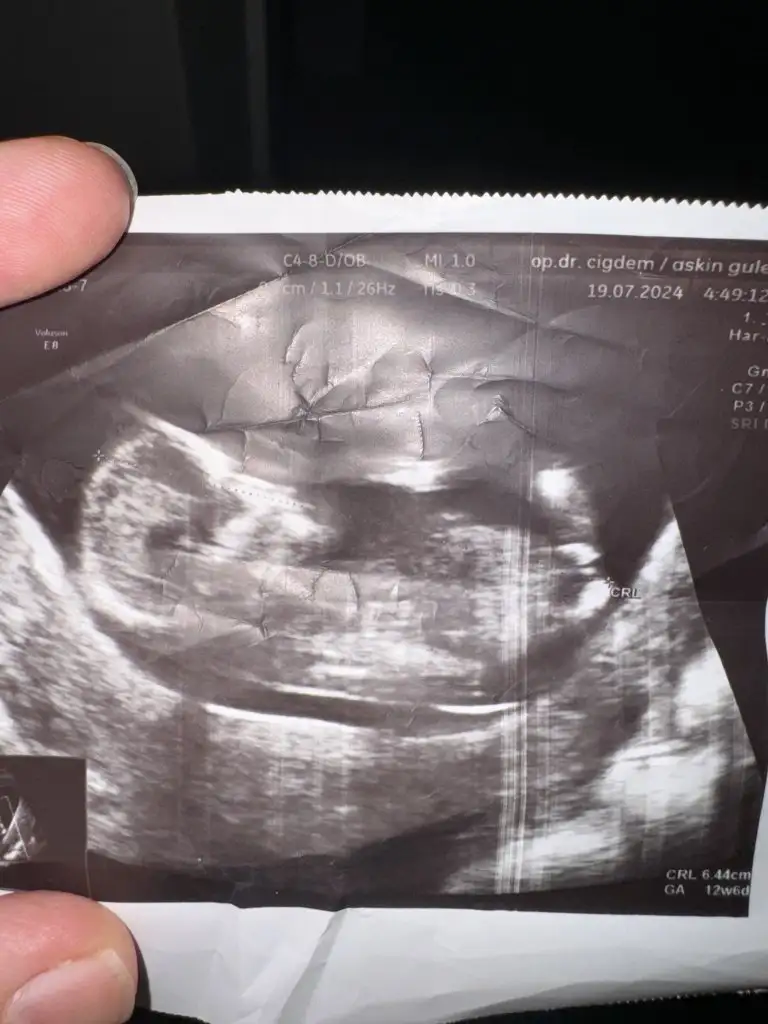

Bana erkek gibi geldi bacak arasıMerhabalar, sizler deneyimlisinizdir ultrason görüntümden cinsiyet tahmininde bulunabilecek olan var mı acaba? Şimdiden teşekkürler..

Çok teşekkür ederimBana erkek gibi geldi bacak arası![]()